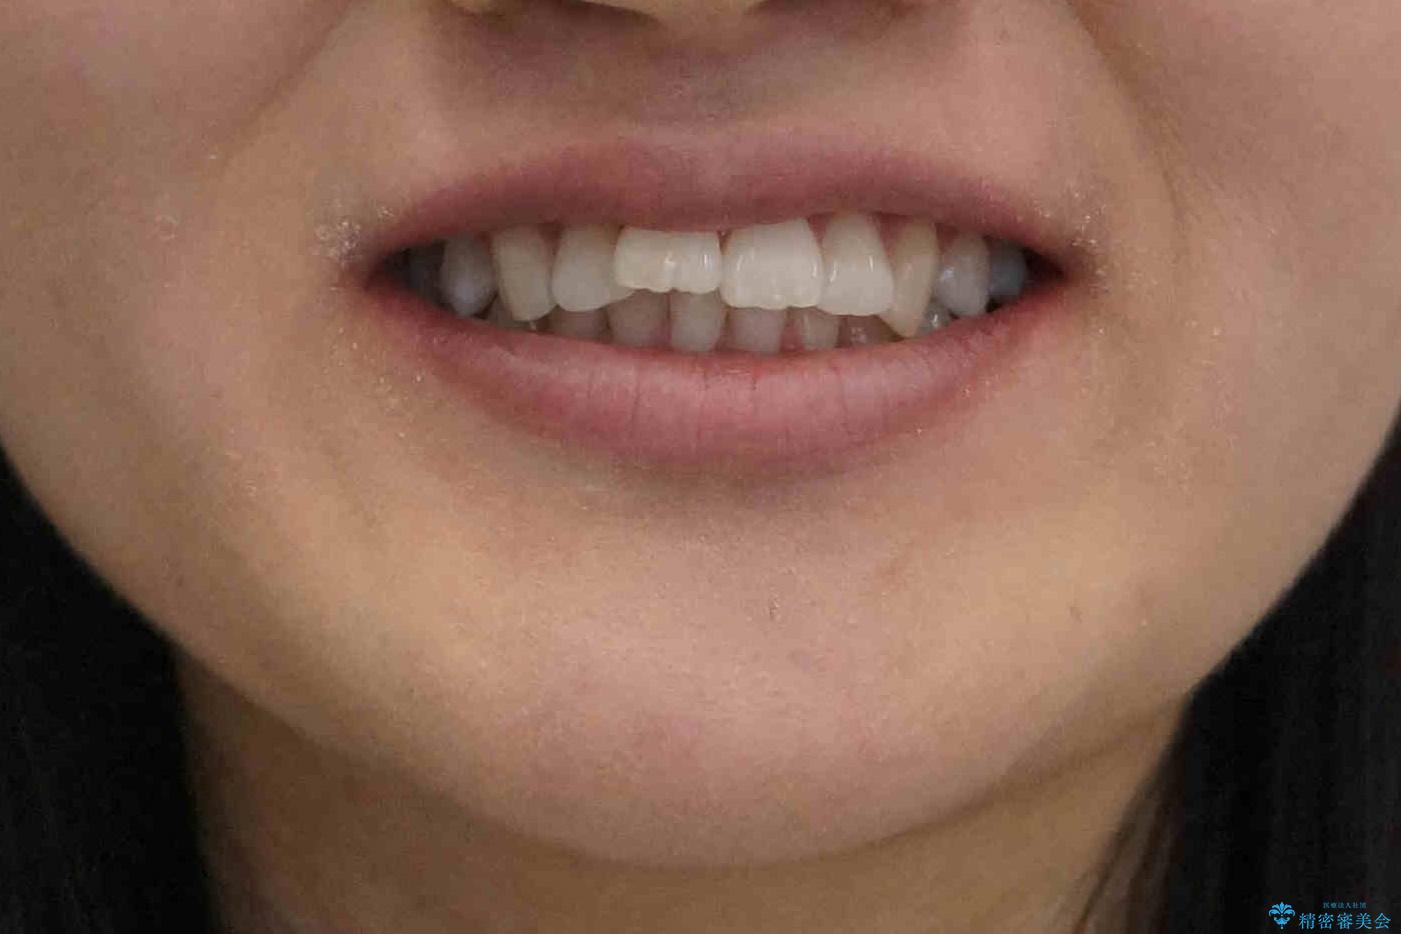

歯を抜かないで出っ歯を治したい

- 前歯が出ていることを主訴に来院。

歯を抜かずにマウスピース矯正をご希望でした。

歯と歯の間をわずかに削り、歯並びを少し横に拡大して並べました。

奥にすき間がなかったため後ろには下げていません。

沢山ひっこめるには4本抜歯でワイヤーの選択肢もありましたが、抜かないでできる範囲をご希望されました。

とがった形の歯列を整えるだけでもだいぶ印象は変わると思います。

今回歯列を広げた結果、上顎犬歯の歯肉は多少退縮しています。